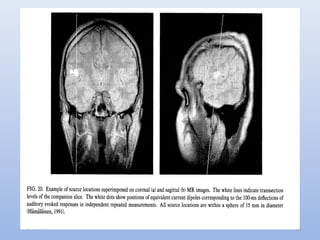

Dipolar Distribution of the Magnetic Flux

• In the following figure, one set of concentric circles represents

the magnetic flux exiting the head and the other represents

the re-entering flux

• This is called a dipolar distribution

• The two points where the recorded flux has the highest value

are called extrema

• The flux density diminishes progressively, forming iso-field

contours

 From the dipolar distributions, we can determine some

characteristics of the source

1. The source is below the mid-point between the extrema (points

where recorded flux has highest value)

2. The source is at a depth proportional to the distance between

the extrema

◦ Extrema that are close together indicate a source close to the

surface of the brain

◦ A source deeper in the brain produces extrema that are

further apart

1. The source’s strength is reflected in the intensity of the recorded

flux

2. The orientation of the extrema on the head surface indicates the

orientation of the source